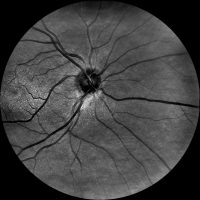

Dzięki technologi SLO – Scanning Laser Ophthalmoscope, podczerwieni oraz wiązki zielonego laseru, jesteśmy wstanie wykonać bardzo dokładny zrzut dna oka, dzięki czemu wykryjemy praktycznie każde zmiany w gałce ocznej. W realizacji takiego skanu nie potrzebne jest zakroplenie oka co znacznie usprawnia nam diagnostykę pod katem szybkości badania czy samopoczucia osoby poddanej tejże czynności. Badanie ma na celu wykrycie zmian w oku jak: jaskra, zaćma, zatory żylne, męty, retinopatie cukrzycową czy AMD(zwyrodnienie plamki żółtej), Pełna wizyta obejmuje:

– skanowanie laserowe dna oka,